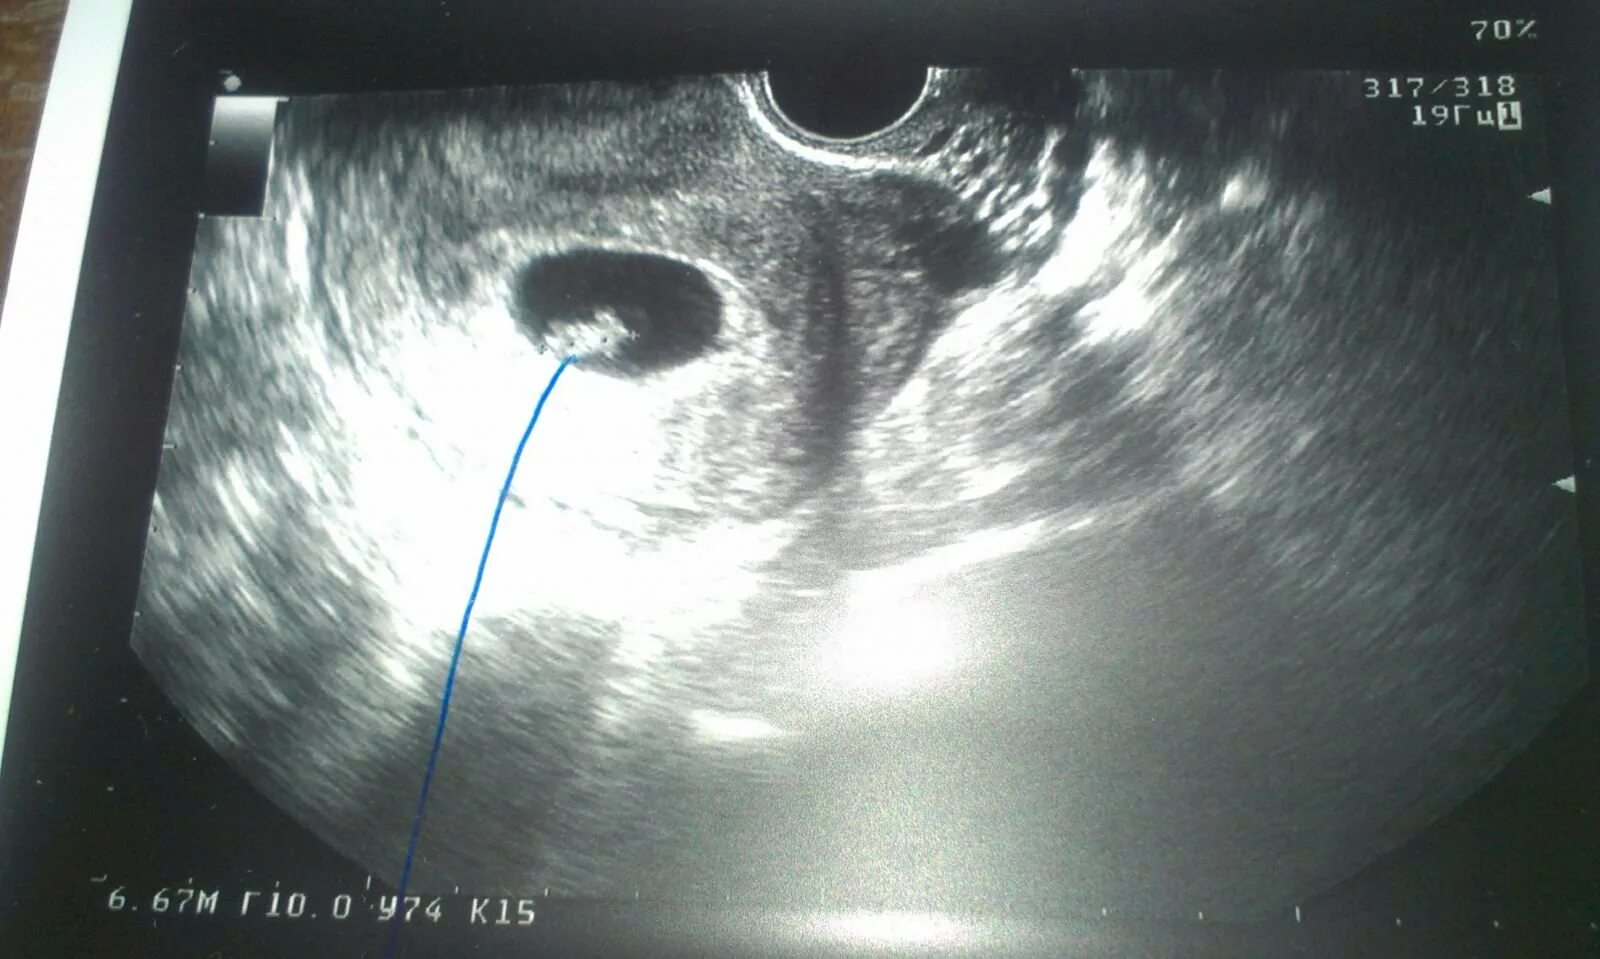

Плодное яйцо 3 мм